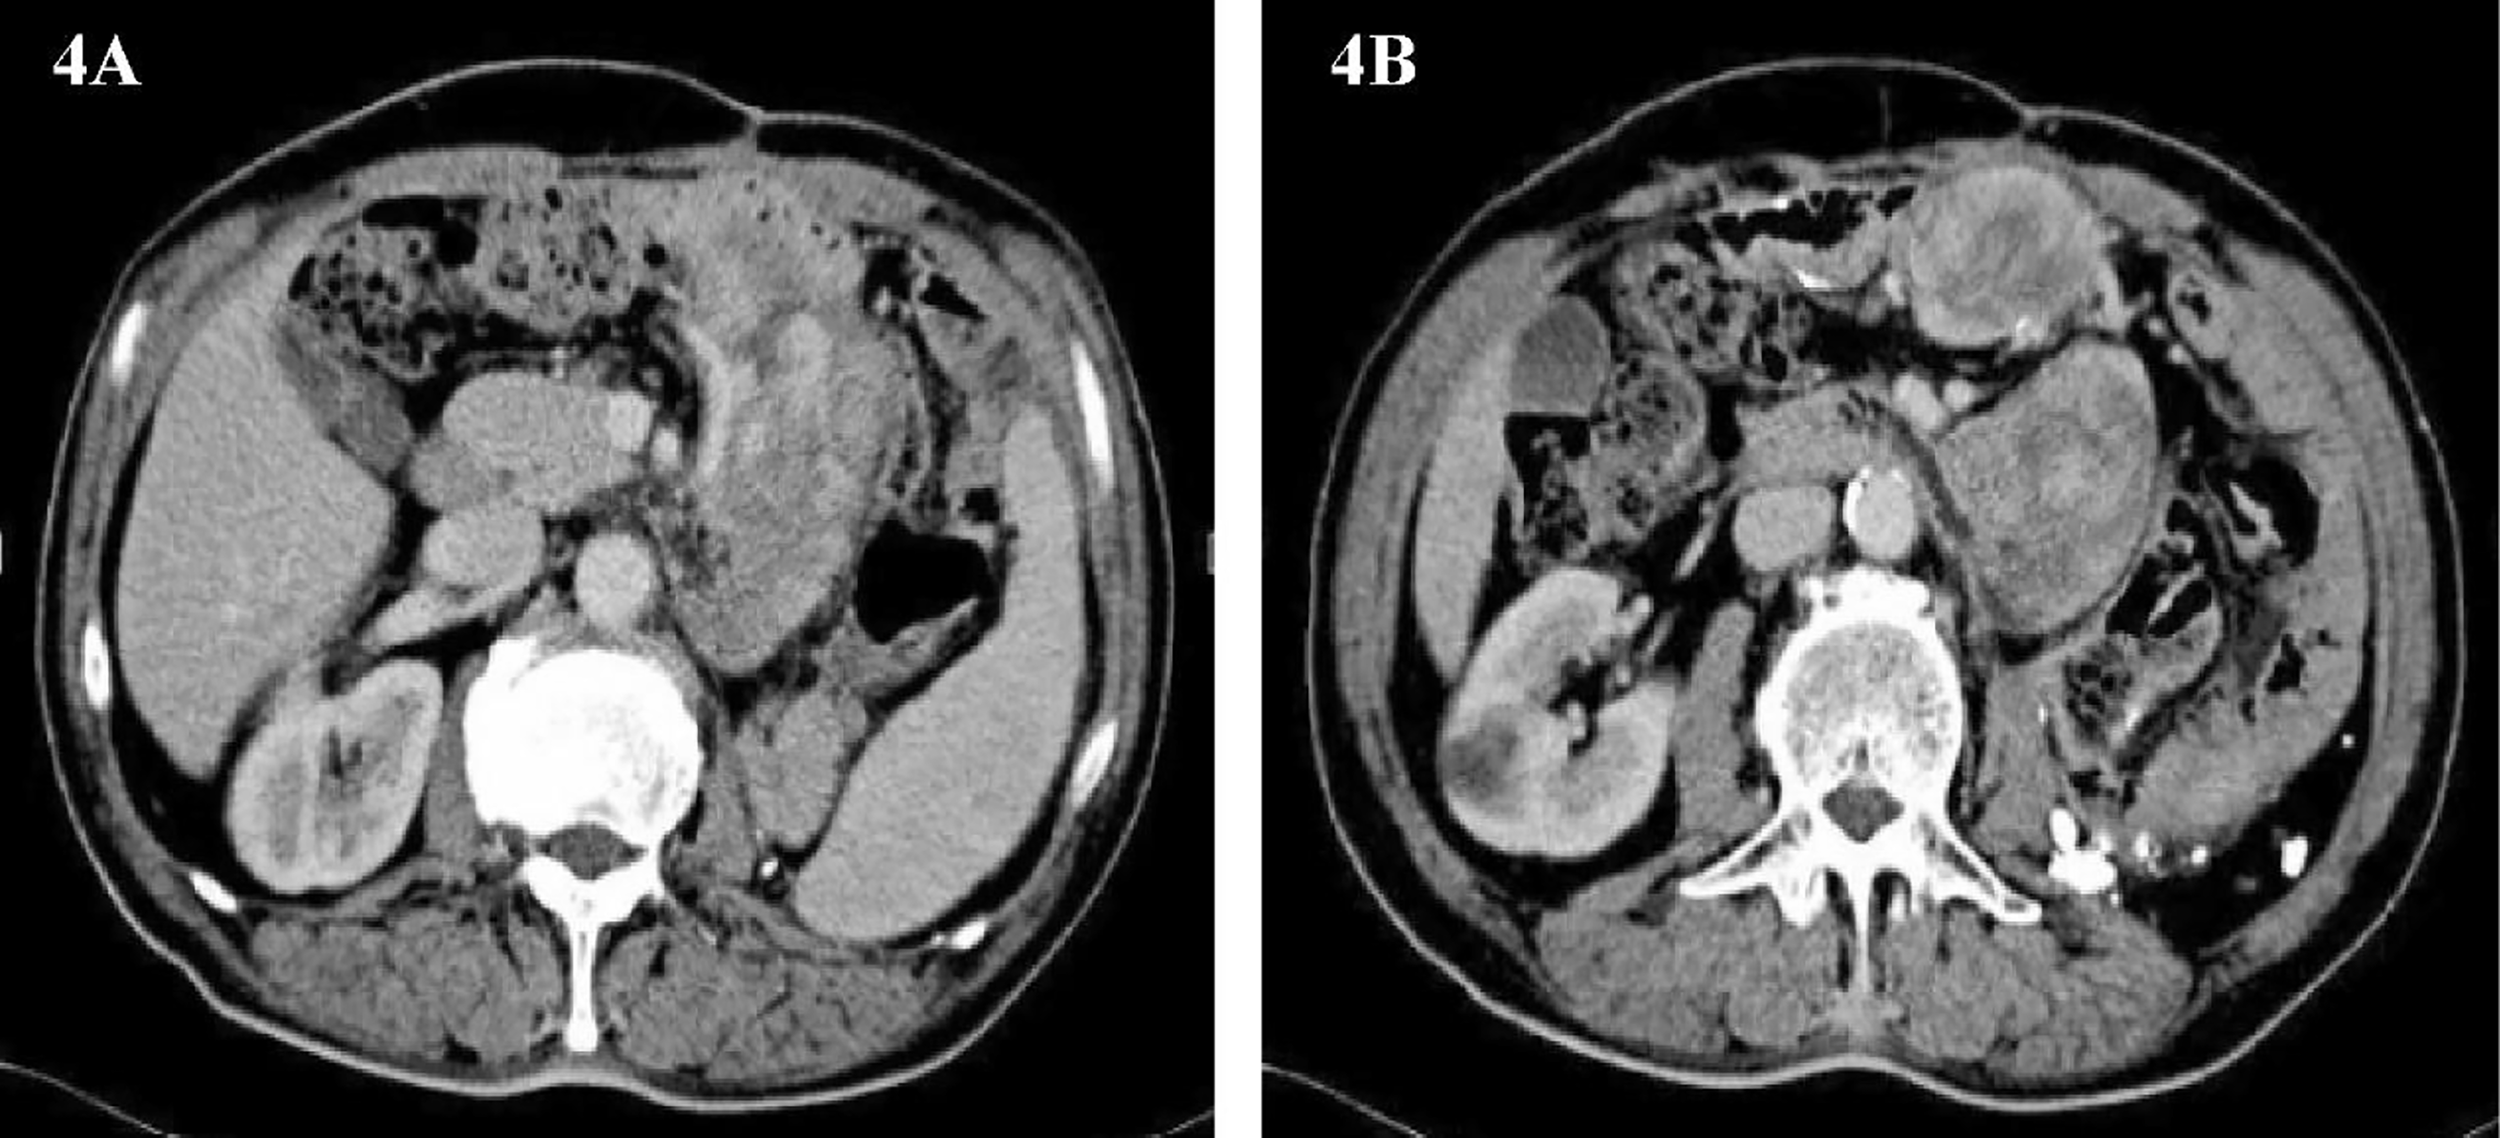

Only 3 months have passed since the last operation, the imaging examination showed that the tumor had recurred. In consideration of the patient’s physical condition, no treatment will be carried out temporarily, and the patient will be asked to recheck regularly. After 3 months, abdominal CT showed multiple masses of soft tissue density shadow in the abdominal cavity, and the lesions were significantly larger than before (Figures 4A, B). Only half a year after the patient’s last operation, we decided to have a multidisciplinary consultation. The chief surgeon invited experts from oncology, pathology, radiotherapy, medical imaging and urology departments to discuss. After multi-disciplinary discussion, it is recommended to perform surgery for the patient again. On January 21, 2015, we performed the fourth operation for the patient. Operation name: Resection of multiple retroperitoneum tumors + Partial jejunum resection + Partial resection of the ileum + Duodenal jejunum end-to-end anastomosis + Partial resection of small mesentery + Partial splenectomy + Abdominal wall tumor resection + Lysis of Intestinal Adhesions + Retroperitoneal lymphatic tissue dissection. The postoperative pathology was dedifferentiated liposarcoma, and some areas showed rhabdomyosarcoma differentiation and invaded the muscularis of the intestinal wall. Immunohistochemistry: SMA (+), MyoD1(+), Myogenin (+), Desmin (-), Caldesmon (-), S-100(-). The Ki67 positive rate is about 30%. In view of the large range of surgical resection, the patient was transferred to the intensive care unit for transition. The patient was transferred back to the general ward on the 3rd day after surgery and was discharged from the hospital on February 2, 2015.

Figure 4

(A, B) Abdominal image before the fourth operation.